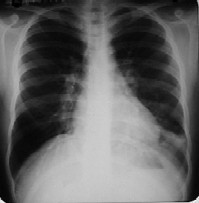

Después de la sorpresa inicial, se detiene a mirar la radiografía. ¿Qué puede ver en ella?